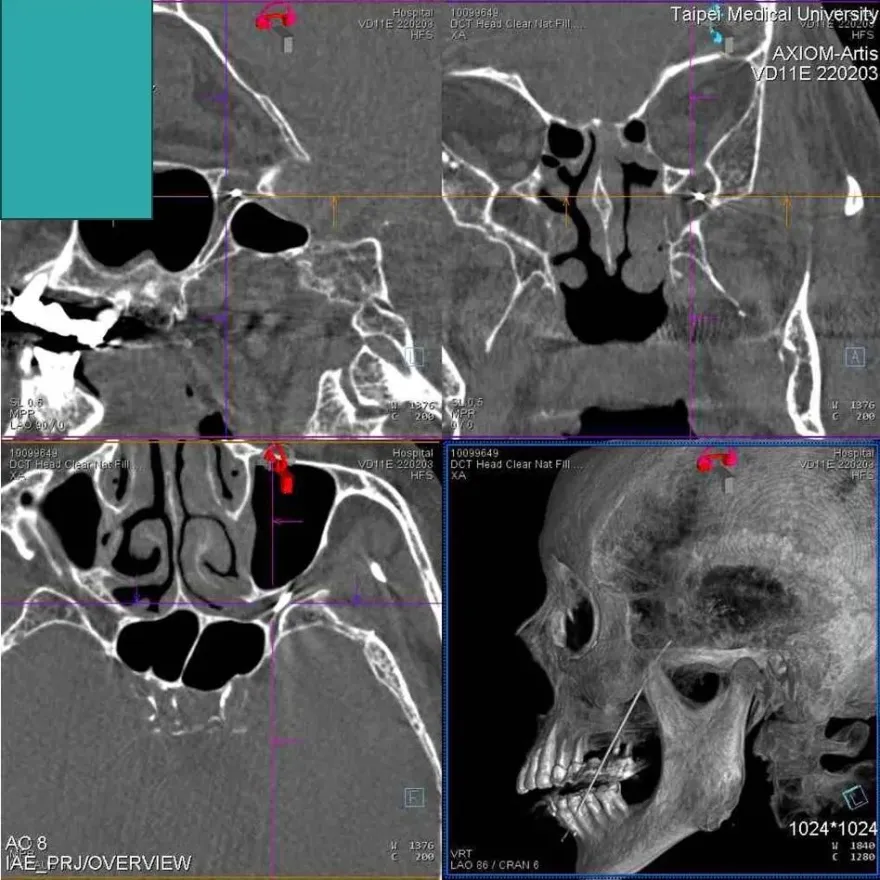

甲狀腺射頻消融手術

壓迫氣管

呼吸不順

吞嚥困難

全身麻醉

亞洲大學附屬醫院

甲狀腺腫瘤